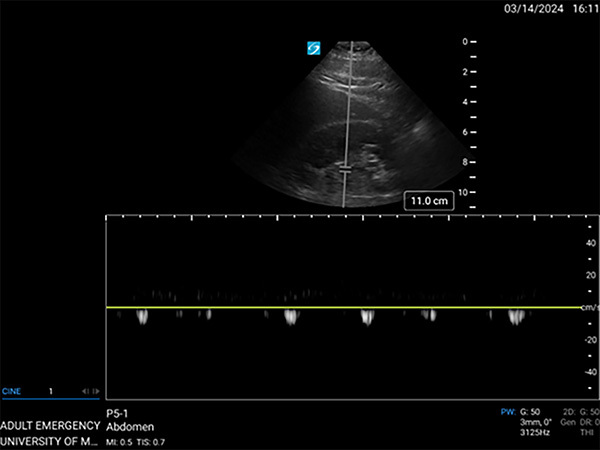

Renal venous Doppler US also can be used for volume status assessment since an elevated central venous pressure (CVP) directly affects renal venous flow (RVF). The exam is performed by placing the patient in the left lateral decubitus position and identifying the right kidney in the longitudinal plane. The patient then will perform an end-expiratory hold. First, color Doppler should be used to identify an interlobar vein. Then, pulse-wave Doppler is used to assess venous flow.

Under normal conditions, RVF should be continuous, with mild variations during the cardiac cycle.61 With rising CVP, the RVF becomes discontinuous and will then form biphasic and monophasic patterns as it continues to rise.59 (See Figure 4.) Observational studies in non-hospitalized patients with HF have demonstrated that non-continuous intrakidney venous flow is associated with an increased risk of HF exacerbations and death.62,63

Figure 4. Example of Renal Venous Doppler Ultrasound in a Patient with Acute Decompensated Heart Failure |

Image shows the discontinuous, monophasic pattern of renal venous flow (RVF), consistent with rising central venous pressure (CVP). Source: Jonathan Hurst, MD. |